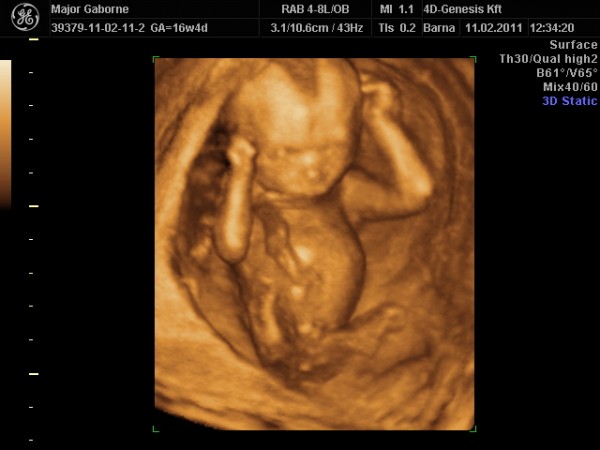

Ultrahang, első percben terpesztés, kuki!

Májusban születik.